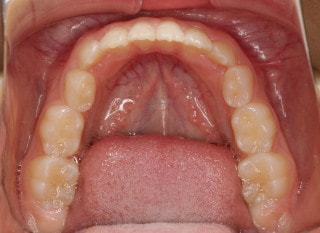

小児期第一段階

終了時